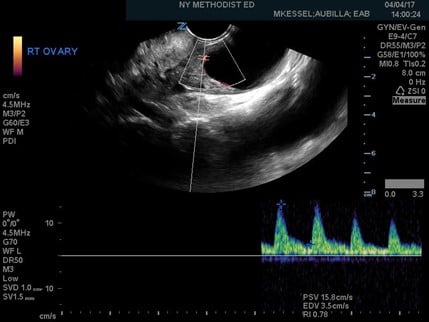

Figure 3. Ovarian torsion indicated by a high resistive index of 0.78

Once the gray-scale features have been delineated, Doppler flow can be utilized. Power Doppler should be used as it provides better sensitivity for slow or low blood volume states. Doppler findings will show either no blood flow to the ovary or asymmetric blood flow when compared with the other side. Once the power Doppler button is pressed, a gate will appear on the screen. The gate should then be placed over, and adjusted to, the size of the signal coming from the ovary. Once activated, a pulsed-wave Doppler tracing will appear on the screen. Arterial waveforms are pulsatile and have a high-flow pattern, while venous is typically continuous with minimal changes in the velocity of the flow. Resistance to arterial blood flow into the ovary, caused by outflow obstruction, can then be calculated by using the resistive index (RI). The RI is defined as the peak systolic velocity minus end diastolic velocity, divided by the peak systolic velocity, and is usually calculated using the ultrasound machine software on an arterial pulsed-wave Doppler tracing. A value of greater than 0.7, as depicted in Figure 3, indicates high resistance which is concerning for torsion.4